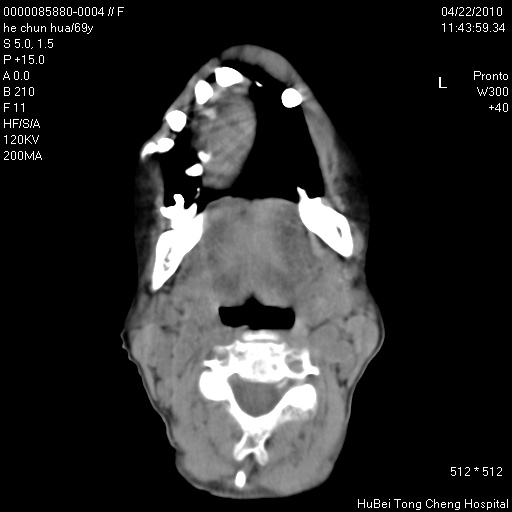

标题: CT25937:女,69Y

硬腭部包块十余年,渐进性增大。

病程长,考虑巨细胞修复性肉芽肿可能性大;

鉴别:神经源性病变、硬结病等。

五楼说得有道理,支持一下。巨细胞修复性肉芽肿好象是外伤出血后引起的修复性改变,骨质呈溶骨性破坏,但病程呈良性过程。